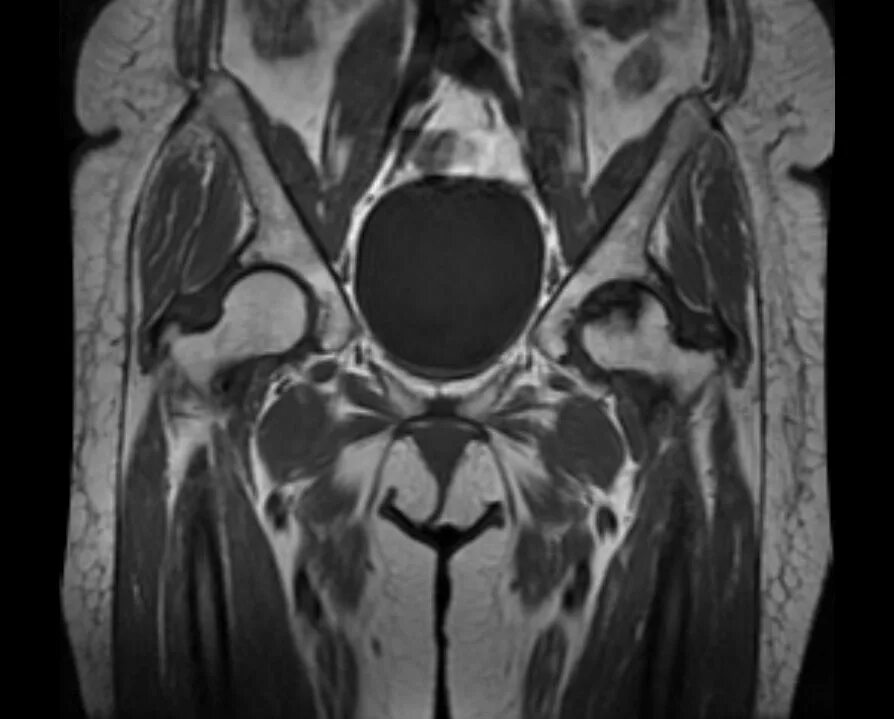

Мрт тазобедренного сустава в минске